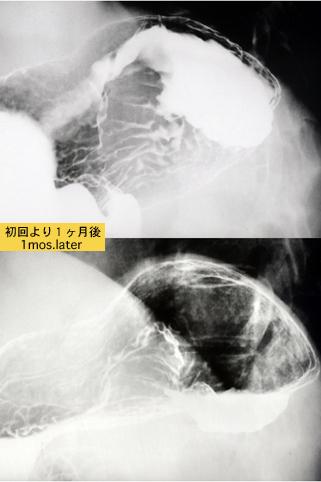

Estenosis de Colon, debido a la pancreatitis que mostró la formación similar al caso del cáncer avanzado del intestino grueso

[Image-ID:6779]

Lesión que asemeja tumoración/infiltración desde órganos contíguos

parte(separada por órganos)

estómago(región)/cuerpo

método de exámen

Rayos X

diámetro mayor del tumor

40 -